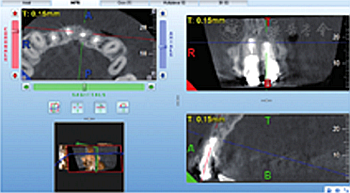

見圖8,圖9,圖10,圖11。分別于術(shù)后3、6個(gè)月時(shí)復(fù)查根尖X線片,8個(gè)月時(shí)復(fù)查錐形束CT并分別進(jìn)行臨床檢查。復(fù)查結(jié)果顯示根尖病變已愈合,根尖無明顯低密度影。臨床檢查叩診正常,無松動(dòng),牙齦位置無明顯變化。

圖11 術(shù)后8個(gè)月復(fù)查錐形束CT截面顯示患者根尖病變已愈合